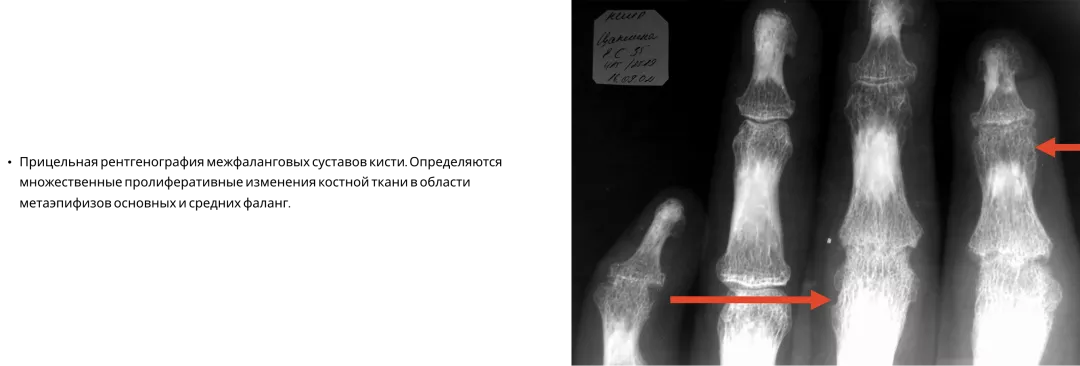

Псориатический артрит3

Псориатический артрит — заболевание, при котором в процесс могут вовлекаться как мелкие, так и крупные суставы, а также позвоночник. Структурные повреждения при ПсА являются основной причиной инвалидизации больных. Вот, к примеру, такой пациент с мутилирующим артритом не сможет выполнить элементарных движений — взять в руки ложку или мобильный телефон, застегнуть пуговицы или завязать шнурки. Все это, конечно, приносит большие страдания пациентам3,9.

Типичные рентгенологические проявления ПсА — костные пролиферации и эрозии4

Image

Frame 24062082 (2).png